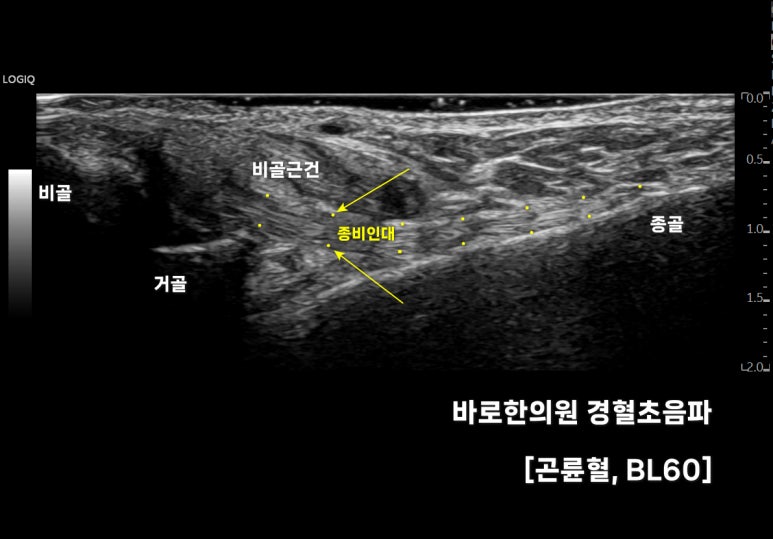

위 영상은

의

표준 초음파 영상인데요.

깊이에 따라

장단비골근건, 종비인대,

비골, 거골, 종골 등이 보입니다.

가장 깊숙하게 있는

는

과 을 연결해줘서

앞 글자를 따

종! 비! 인대라고 부릅니다.

발목을 단단하게 고정해주는

아주 중요한 역할을 하죠.